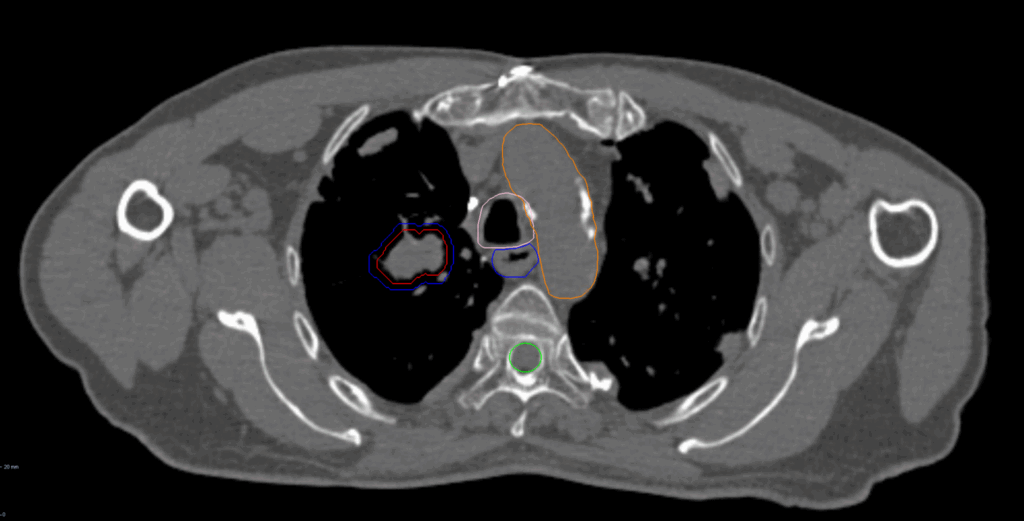

Right Central Lung Metastasis

< View All Plan Studies CYBERKNIFE SYSTEM Right Central Lung Metastasis Case History AGE: 62-year-oldGENDER: Male Medical History Chronic obstructive pulmonary disease (COPD), previous surgery on right lung Chest CT: Suspicious lesion in the right lower lobe PET-CT: hypermetabolic nodule, 3.1cm no evidence of regional or distant metastasis Non-Small Cell Lung Cancer (NSCLC), adenocarcinoma cT2aN0M0, […]